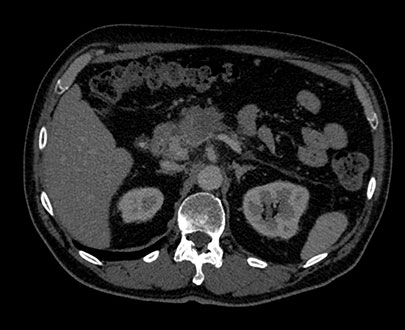

Click the energy level from 40 keV to 200 keV to view structures according to their spectral attenuation properties.

The MonoE view shows synthesized monoenergetic images at predefined keV values from 40 to 200. The appearance of the images changes as the keV values change, even when the window/level settings are unchanged. For example, at lower keV, iodine may appear brighter, and at higher keV, metal artifacts may be reduced.